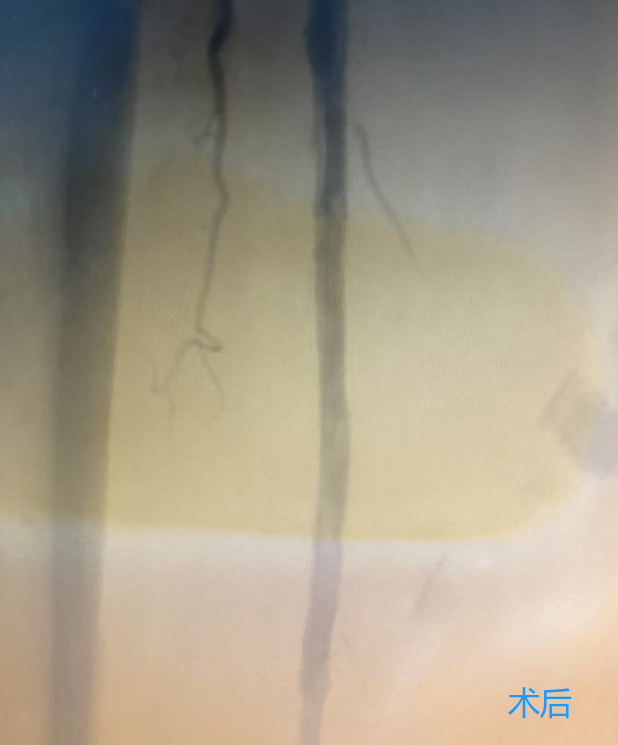

下肢动脉硬化闭塞症的治疗方式包括:生活方式调整、药物治疗、血管腔内治疗、外科手术和康复等方法,可有效缓解症状,提升生活质量。特别是下肢动脉旋切术,作为微创技术,能有效清除血管壁上的斑块。

下肢动脉旋切术的优势

1、无需植入支架:降低了远期并发症的发生率,如血栓和再狭窄等。

2、创伤小,恢复快:减轻了手术痛苦,加速了术后恢复,使患者能迅速回归日常生活。

3、治疗效果显著:改善下肢动脉闭塞,恢复血流畅通,缓解疼痛,提高生活质量。

葫芦岛市第二人民医院血管介入病区现已常规开展下肢动脉旋切术,标志着我市周围血管疾病微创技术及相关领域诊疗水平迈上了新台阶。这一技术的广泛应用,结合先进的影像技术,将为更多下肢动脉疾病患者带来福音,让他们重获健康与希望。